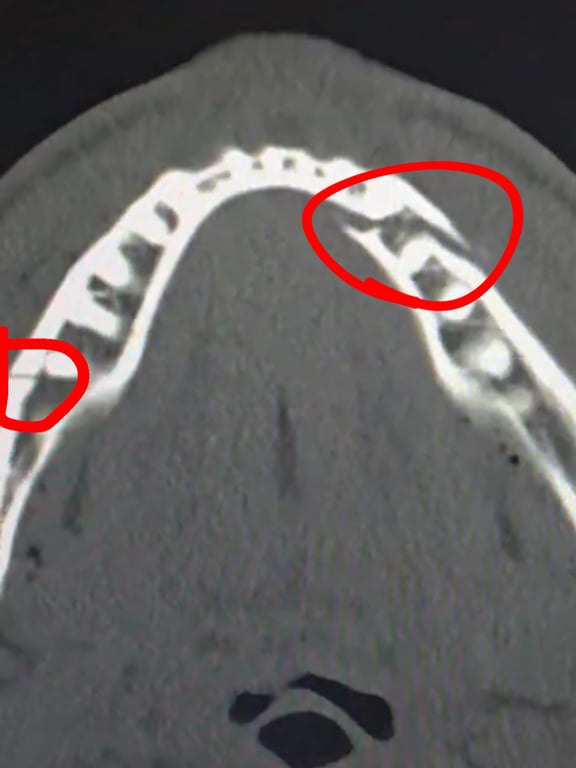

Американец сообщил, что хирургическое вмешательство прошло успешно. Врачи установили по две титановые пластины с обеих сторон челюсти, а также удалили несколько зубов. Ближайшие семь дней Пол будет находиться на жидком питании.

Сломанная челюсть Джейка Пола. Фото: instagram.com/jakepaul